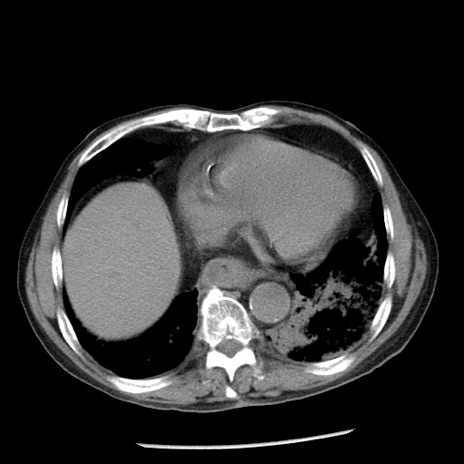

冠状断像

【症例】80歳代男性

【主訴】嘔吐

【現病歴】昨晩2回嘔吐あり、今朝になっても嘔吐あり。来院。

【既往歴】胃潰瘍

【身体所見】意識清明、BT 37.6℃、BP 166/95mmHg、HR 100bpm、SpO2 97%、腹部:平坦・軟、腸蠕動音聴取良好、圧痛なし。

【データ】WBC 21900、CRP 1.46